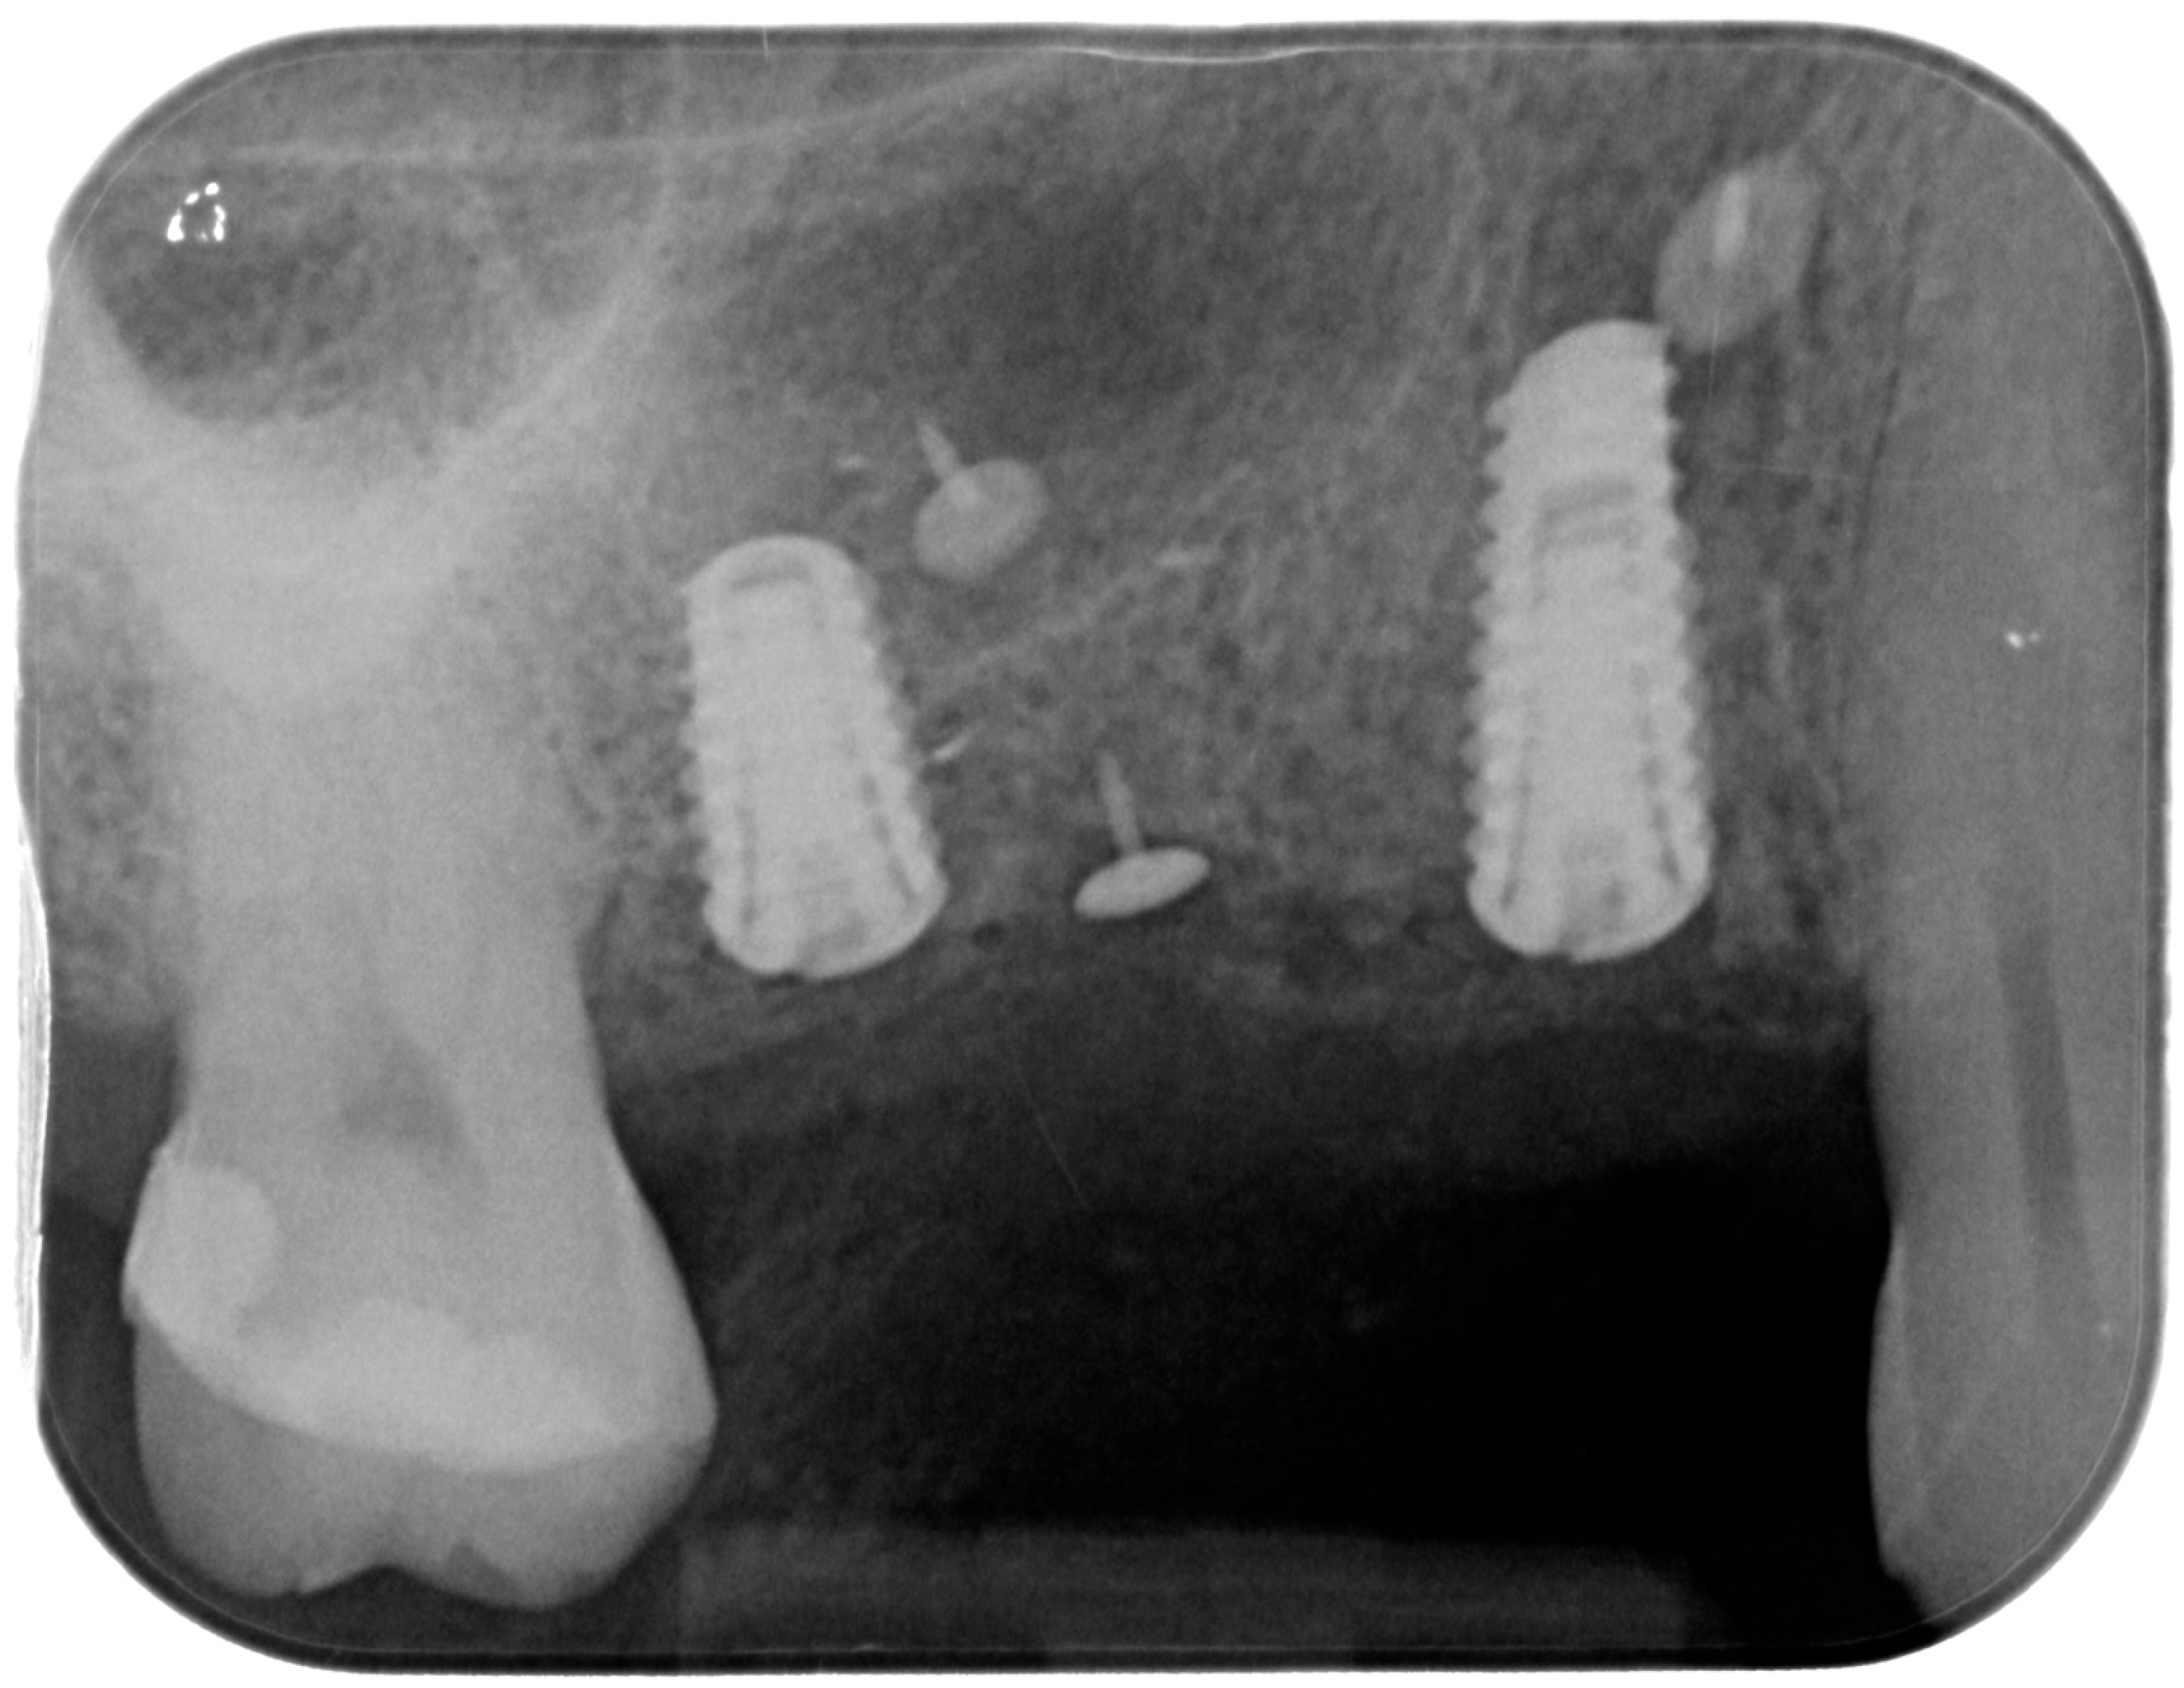

At this point, implants were placed according to the manufacturer’s instructions in a prosthetically ideal position with the aid of the surgical stent (Figure 3 and Figure 4).

Figure 4. Implant positioning and cover screws in place.

Figure 8. Postoperative intraoral X-ray.